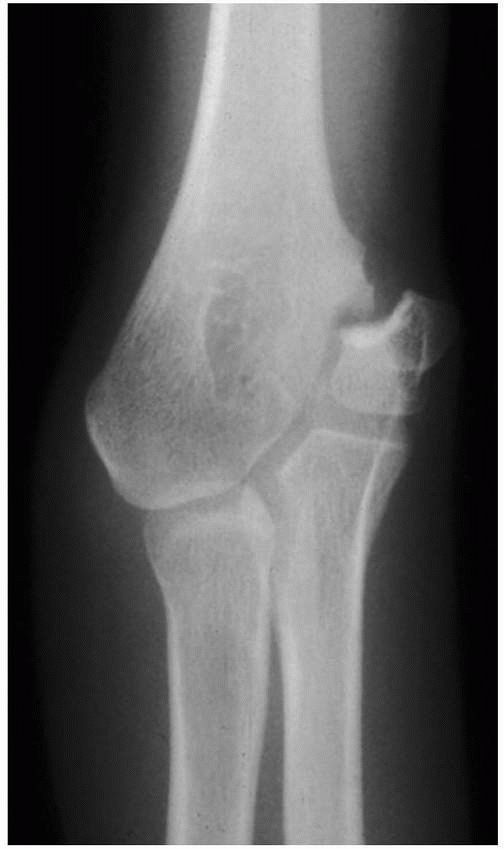

![]() |

FIGURE 15-28 A. The AP radiograph of a 9-year-old boy demonstrates the location of the ossification centers. A common physeal line (arrow) separates the medial and lateral condylar physes. B. Relationship of the ossification centers to the articular surface. The common physis terminates in the trochlear notch (arrow). C. Location of the usual fracture line involving the medial condylar physis (arrows).